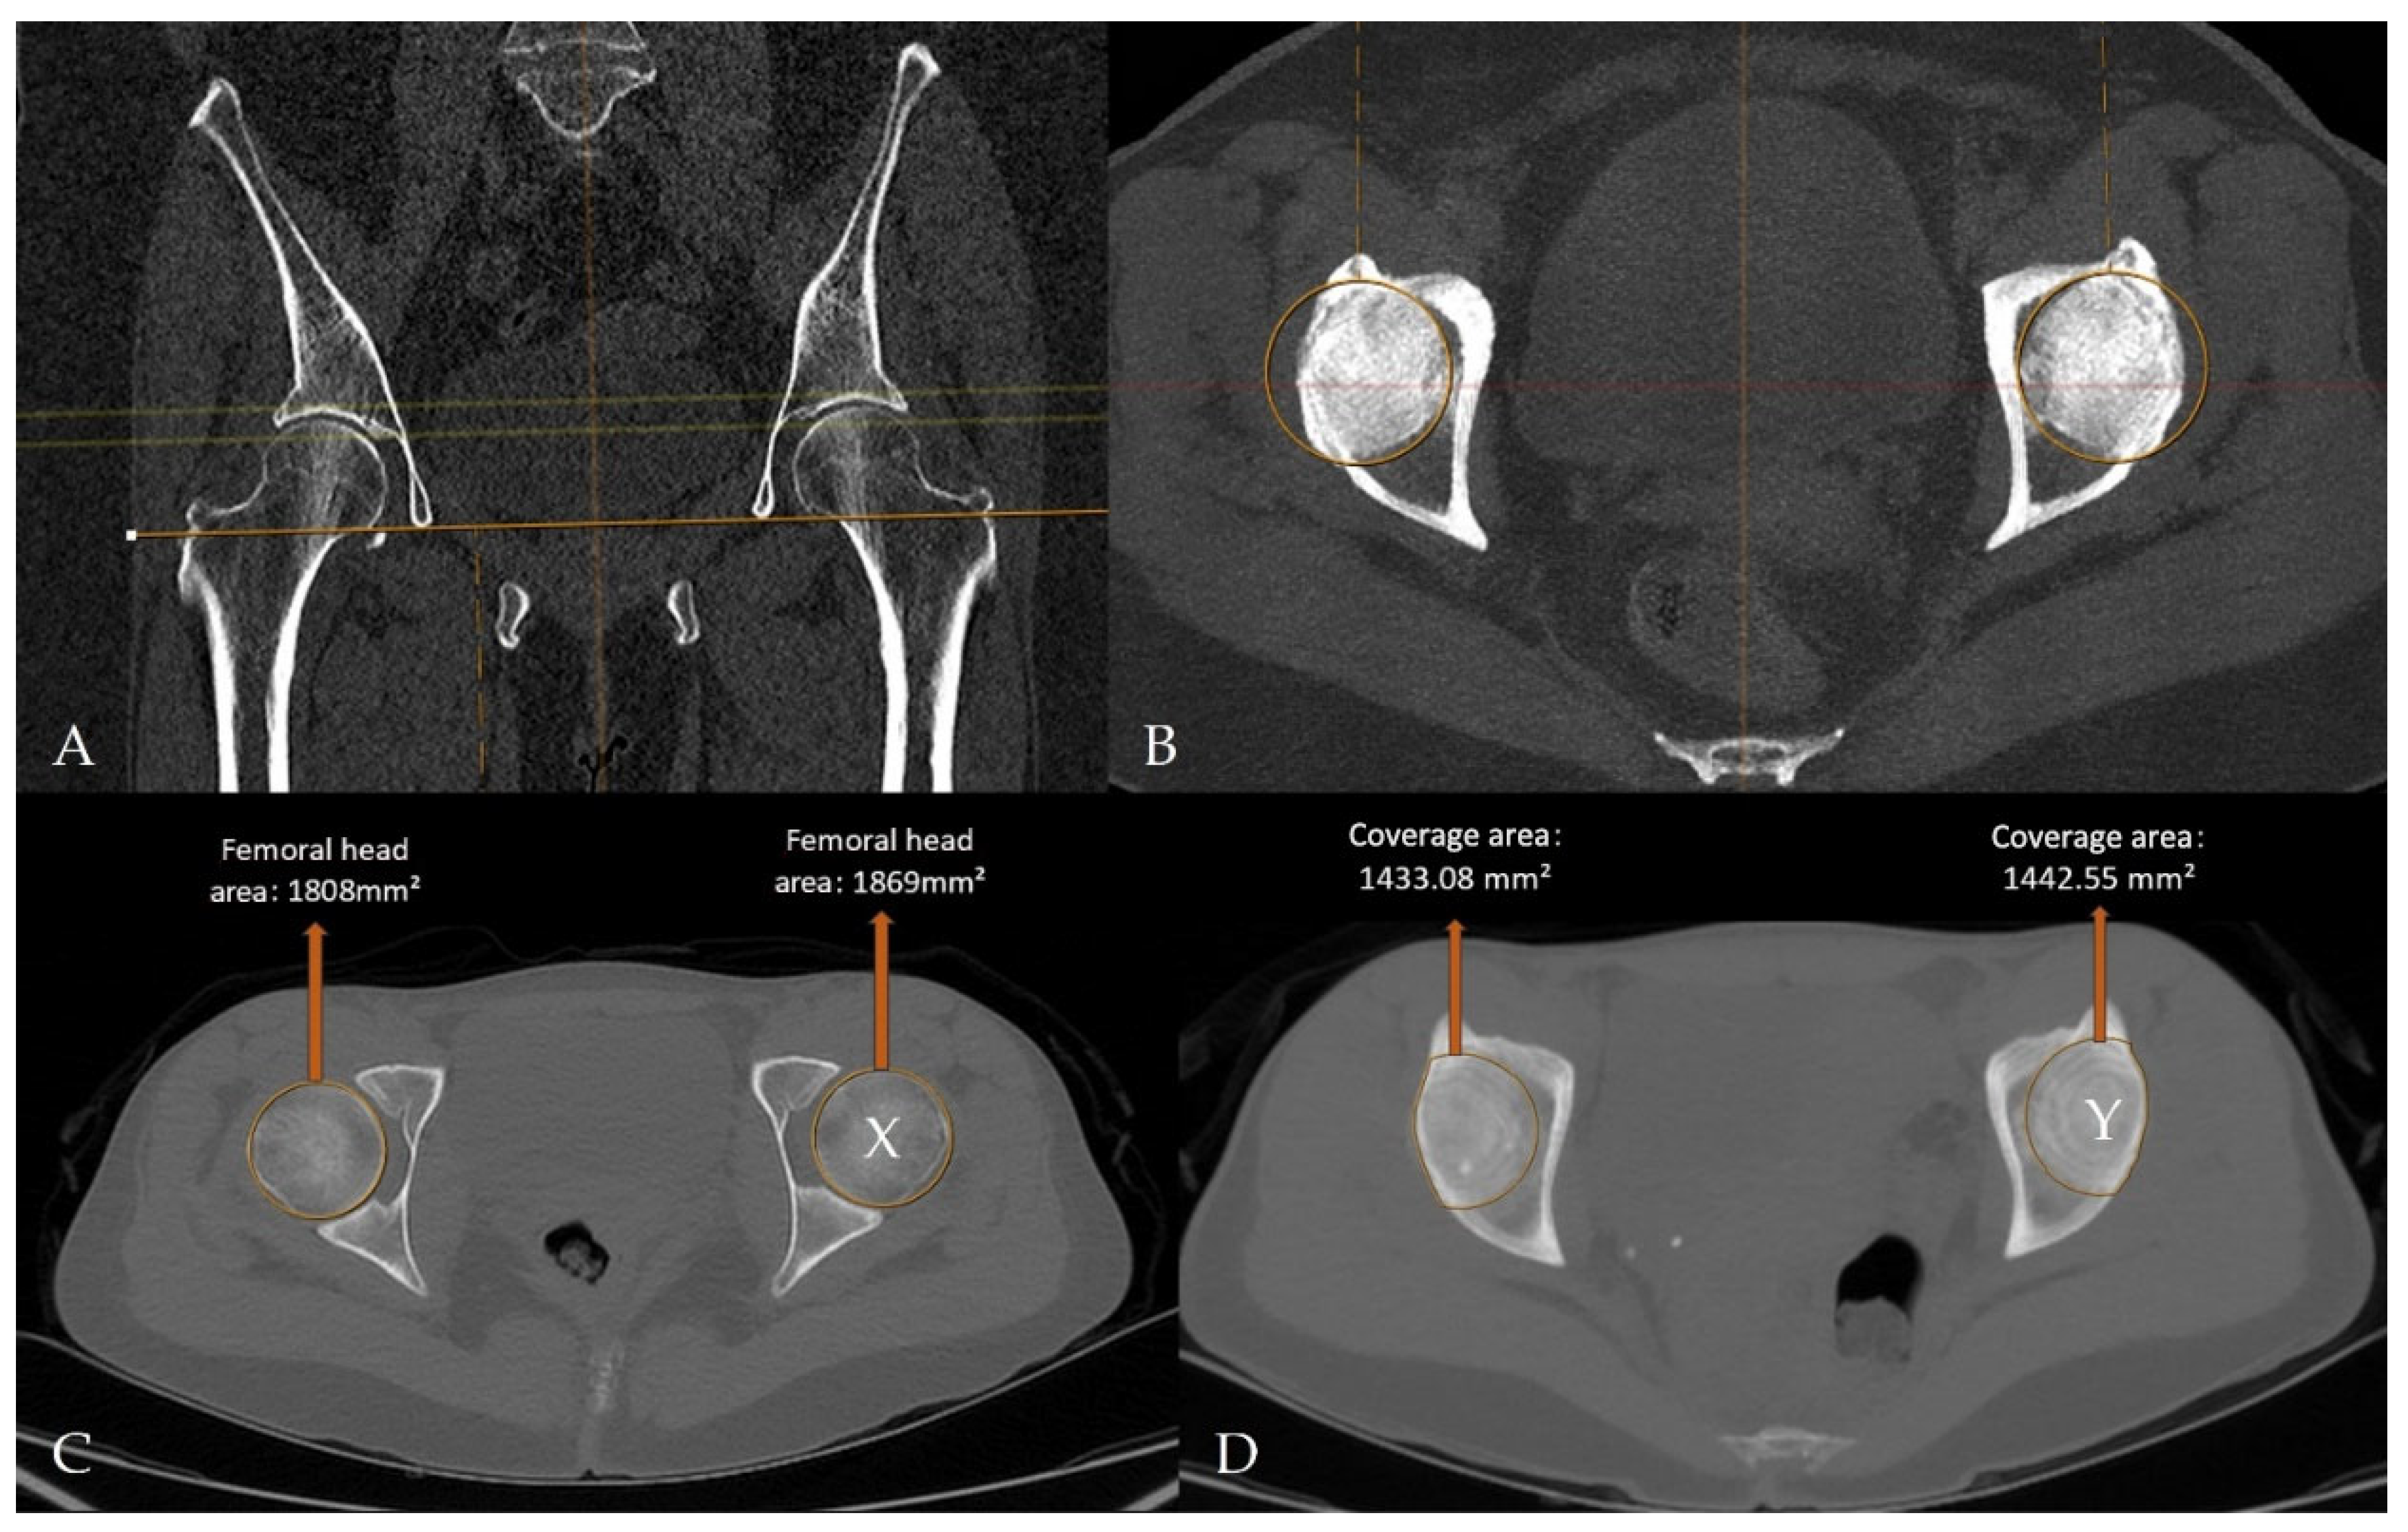

Imaging data were retrospectively retrieved from the SECTRA PACS workstation (IDS7, version 24.2.16.6066; Sectra AB, Linköping, Sweden). Cam-type FAI was defined by an alpha angle of ≥60°, whereas pincer-type FAI was defined by an LCEA of ≥40° (Figure 4) [16,17,18,19]. For CT-MIP evaluation, the maximal cross-sectional area of the femoral head was initially measured on axial CT images using a circular region of interest (ROI). MIP reformatted images with a slab thickness of 10 mm were subsequently generated to enable a comprehensive single-slice evaluation of the acetabular roof. The acetabular coverage area was calculated by manual freehand delineation of the acetabular roof margins covering the femoral head, while preserving the femoral head contours. The ACI was defined as the ratio of the acetabular coverage area to the area of the femoral head (Figure 5).

Figure 5.

CT- and MIP-derived images illustrate quantitative assessment of femoral head morphology and acetabular coverage on a radiology workstation. (A,B) Axial MIP reformats aligned using the teardrop landmarks, demonstrating CT-MIP processing on the imaging workstation. (C) Maximal femoral head cross-sectional area measured on axial CT images. (D) Acetabular coverage area segmented on multiplanar MIP reconstructions. The acetabular coverage index was calculated as Y/X (right, 0.792632; left, 0.771829).

CT-MIP reconstructions were used to facilitate a global and reproducible evaluation of acetabular coverage. The rationale for using CT-MIP was to integrate information derived from multiple axial slices into a single en-face representation of the acetabular roof, thereby reducing slice-selection bias and enabling standardized quantitative assessment independent of patient positioning. Compared with conventional two-dimensional CT measurements, CT-MIP provides a holistic visualization of acetabular overcoverage and allows calculation using routinely available workstation tools without the need for dedicated software.